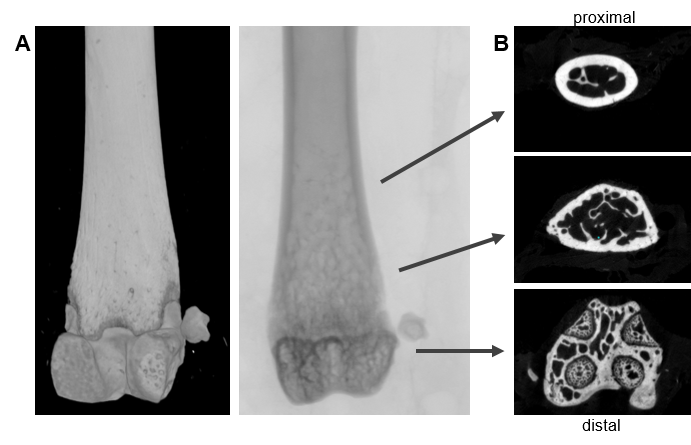

Fig. 8: Microcomputer tomography (µCT) of mouse distal femur. (A) longitudinal view of distal femur (B) transaxial view from distal to proximal; bottom: transaxial view of the epiphyseal reagion of the femur; middle: trabecular bone, transaxial view of the metaphyseal region; top: transaxial view of diaphyseal region. Scan options: X-ray voltage: 70 KV, X-ray current: 200 µA, filter: Al 0.5 mm, image pixel size: 4 µm, tomographic rotation: 180°, rotation step: 0.200°, frame averaging: 8, scan duration: 1h15min. Pictures provided by Sabrina Sapski, Department II.